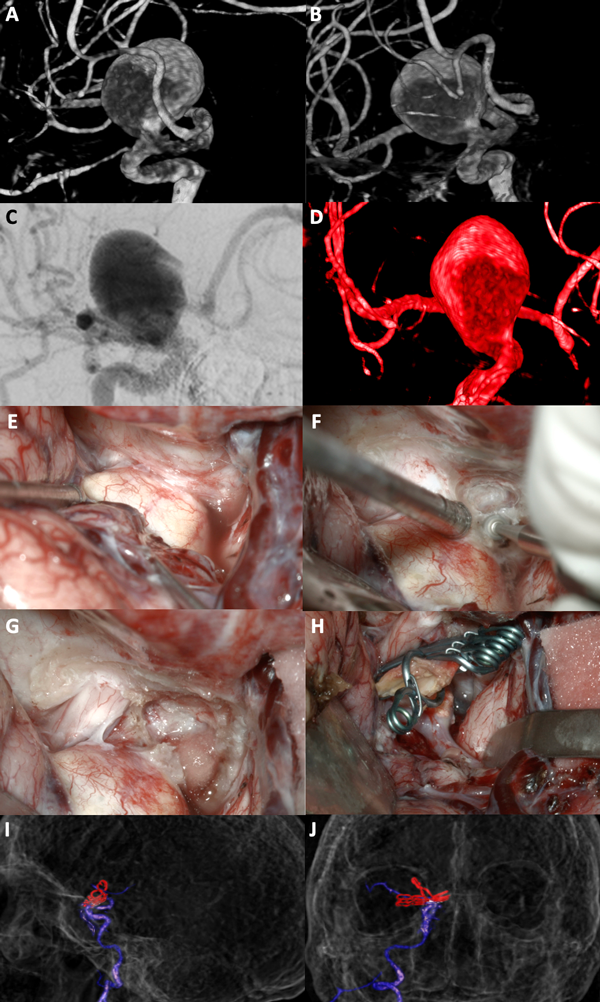

Figura 8. A-D: Se aprecian imágenes de arteriografía cerebral y reconstrucción tridimensional de la misma que evidencian un aneurisma carótido oftálmico derecho gigante. E-H: Fotografías intraoperatorias donde observamos la cisterna óptico-carotidea; es visible el saco aneurismático gigante, apenas visible el nervio óptico comprimido por el aneurisma. Dado el tamaño de la lesión se realiza una clinoidectomía anterior total y sección del anillo dural distal logrando una adecuada exposición del cuello del aneurisma. Se muestra la exclusión del aneurisma con múltiples clips quirúrgicos. G-H: Imágenes de arteriografía cerebral post operatoria con reconstrucción tridimensional que evidencian la exclusión completa del aneurisma.